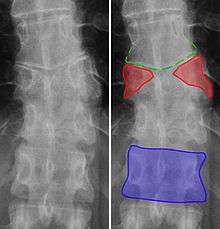

Congenital block vertebra in the lumbar spine (partial vertebrae 3 and 4). The rear portion of the disc still exists.